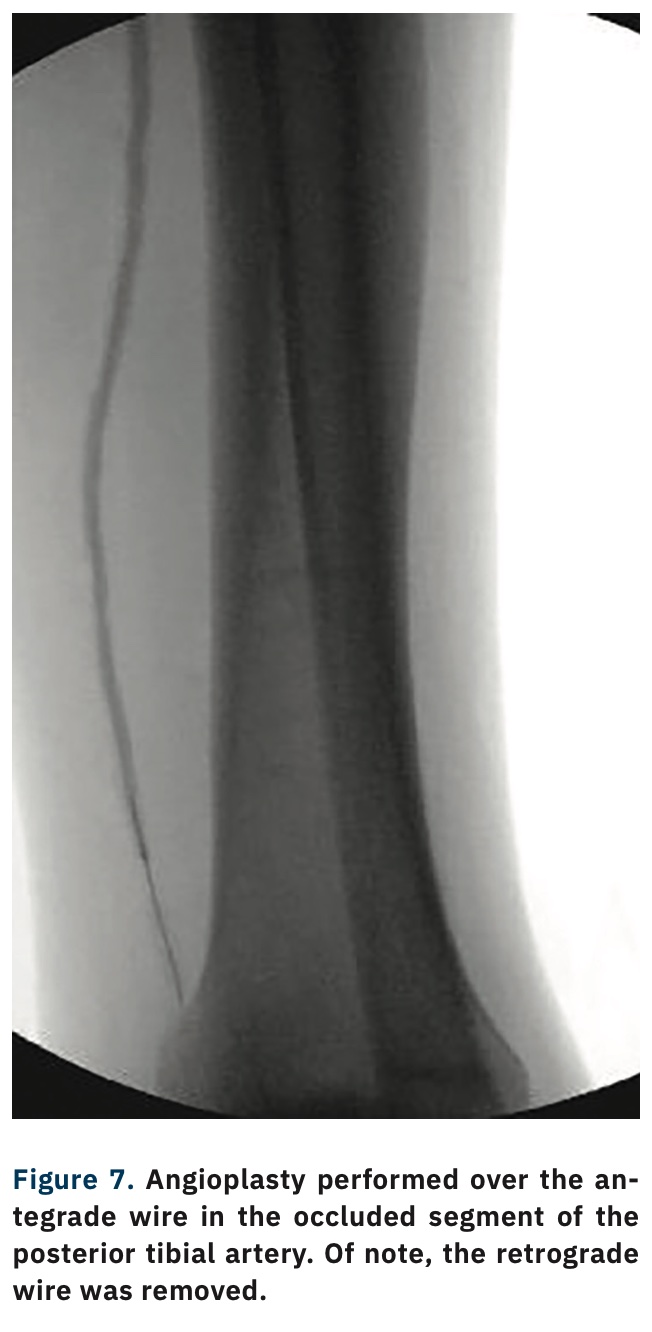

TCTAP C180 Reverse CART Technique in Above Knee Peripheral CTO Cart And Reverse Cart Technique Stent reverse cart entails creation of an open target for retrograde guidewire navigation when a stent is. The “stent reverse cart” technique involves deploying a stent within the antegrade dissected plane to create an open target for retrograde crossing. Controlled antegrade and retrograde subintimal tracking (cart) and reverse cart. Two rdr techniques are available: The most commonly used retrograde crossing. Cart And Reverse Cart Technique.